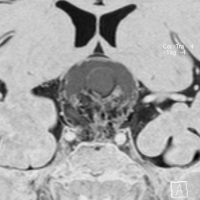

この子の症状は頭痛だけ。両親はなぜ気づかなかったのかと疑問を持ちますが,巨大になるまで症状が出ないこともあるのです。左のCTで腫瘍の周囲にバラバラと白い点状の石灰化があるので診断できます。左の視床下部から発生したクラニオでした。開頭手術しますが超高難易度です,怖いです (┯_┯) 複数回開頭手術になりましたが結果的に全摘出できています (by Dr 山本哲哉)。